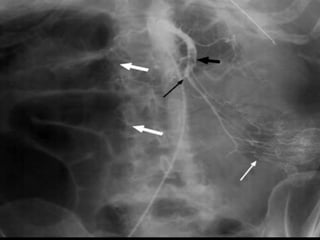

Post OP - Diffuse vasospasm

without occlusions.

Post Papaverine infusion

Arteriogram 24 hr later.

Reversal of vasospasm.

Role of interventionalradiology  NOMI- selective catheter-directed administration of vasodilating agents  Catheter directed thrombolysis  Percutaneous transluminal angioplasty  Fenestration of the aortic dissection.

Post OP -Diffuse vasospasm without occlusions. Post Papaverine infusion Arteriogram 24 hr later. Reversal of vasospasm.